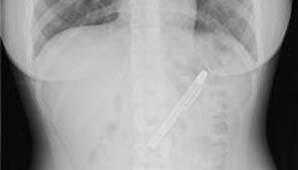

La radiografía que le hicieron en el hospital de Taipei, en Taiwán, no dejaban dudas que la lapicera estaba ahí y la estudiante no tenía la menor idea de cómo había llegado ahí. Según comentó, puede que la introdujera en su organismo el día que celebró la fiesta de fin de exámenes en la que se pasó de copas.